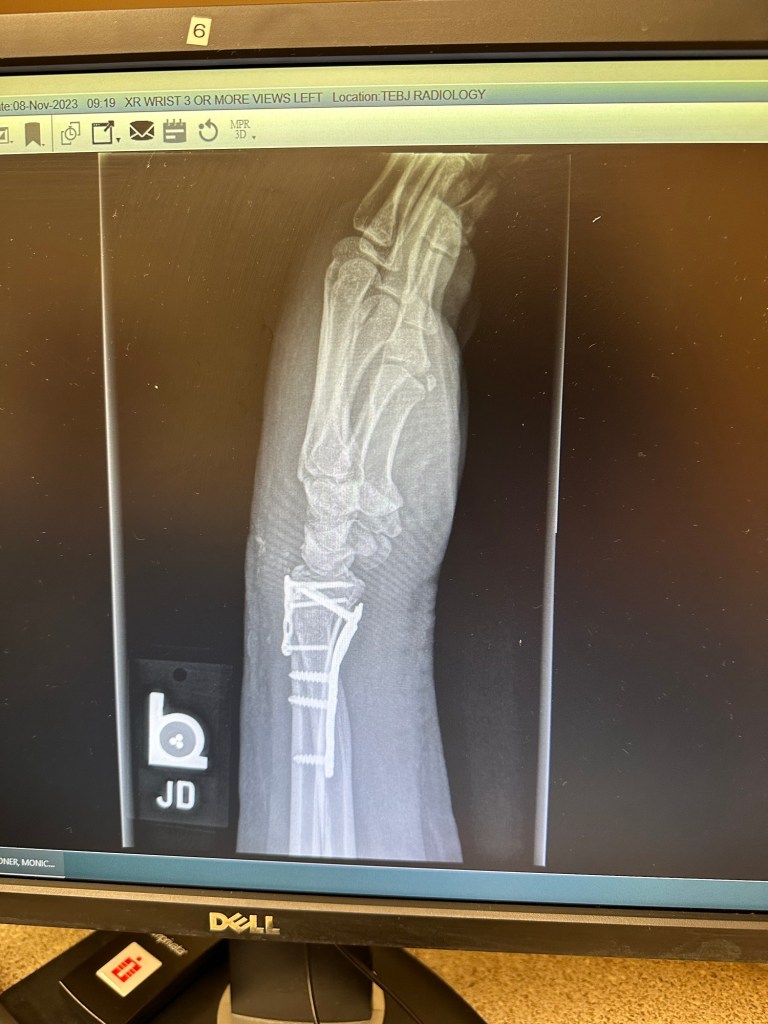

Anyway, Salem bucked several times. I came off and ended with a crushed wrist that required surgery. Shortly after, my day job “got really interesting” and two weeks post-surgery required travel and a lot of overtime. My left hand was virtually useless anyway so Salem got a 30 day break from training. So here I am with a bum wrist, a not very tame mustang, and 9 months to see if I can make this goal happen. Its not looking good, since I’ve wisely decided to find a colt starter with better facilities to put 30 or so rides on her before I try it again.